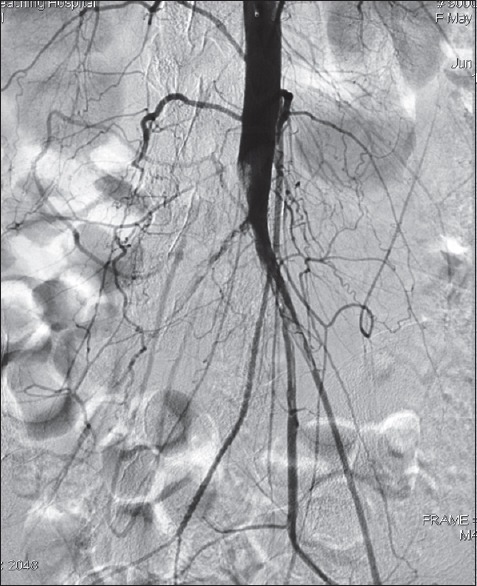

Materials and methods: We present our first 25 cases of peripheral angioplasty in Northwestern Nigeria. The clinical diagnosis of peripheral artery disease was confirmed with Doppler ultrasound and angiography. Angioplasty was done either through femoral or brachial artery approaches. The patients were monitored for minimum of 6 months with serial clinical and Doppler ultrasound examinations.

Results: Our patients consist of 19 males and 6 females. Their ages ranged from 20 to 80 years with a mean of 54 ± 17.5 years. There were 13 hypertensive and 15 diabetic patients while 5 patients have co-morbidities of diabetes and Hypertension. Although femoral antegrade route is the common access for angioplasty (14 out of 25), seven patients who were treated through the left brachial artery, six of them had either Type C or D aortoiliac disease in addition to distal lesions. At follow-up, 36% had limb amputation while one patient died a day after the procedure. Out of nine patients who had amputation, six are diabetic.

Conclusion: Although more than half of them had improved blood flow with healing ischemic ulcers and reducing claudications, still substantial number of our patients often present late with severe peripheral artery disease. As a result, we had to resort to cumbersome arterial access and high amputation rate.